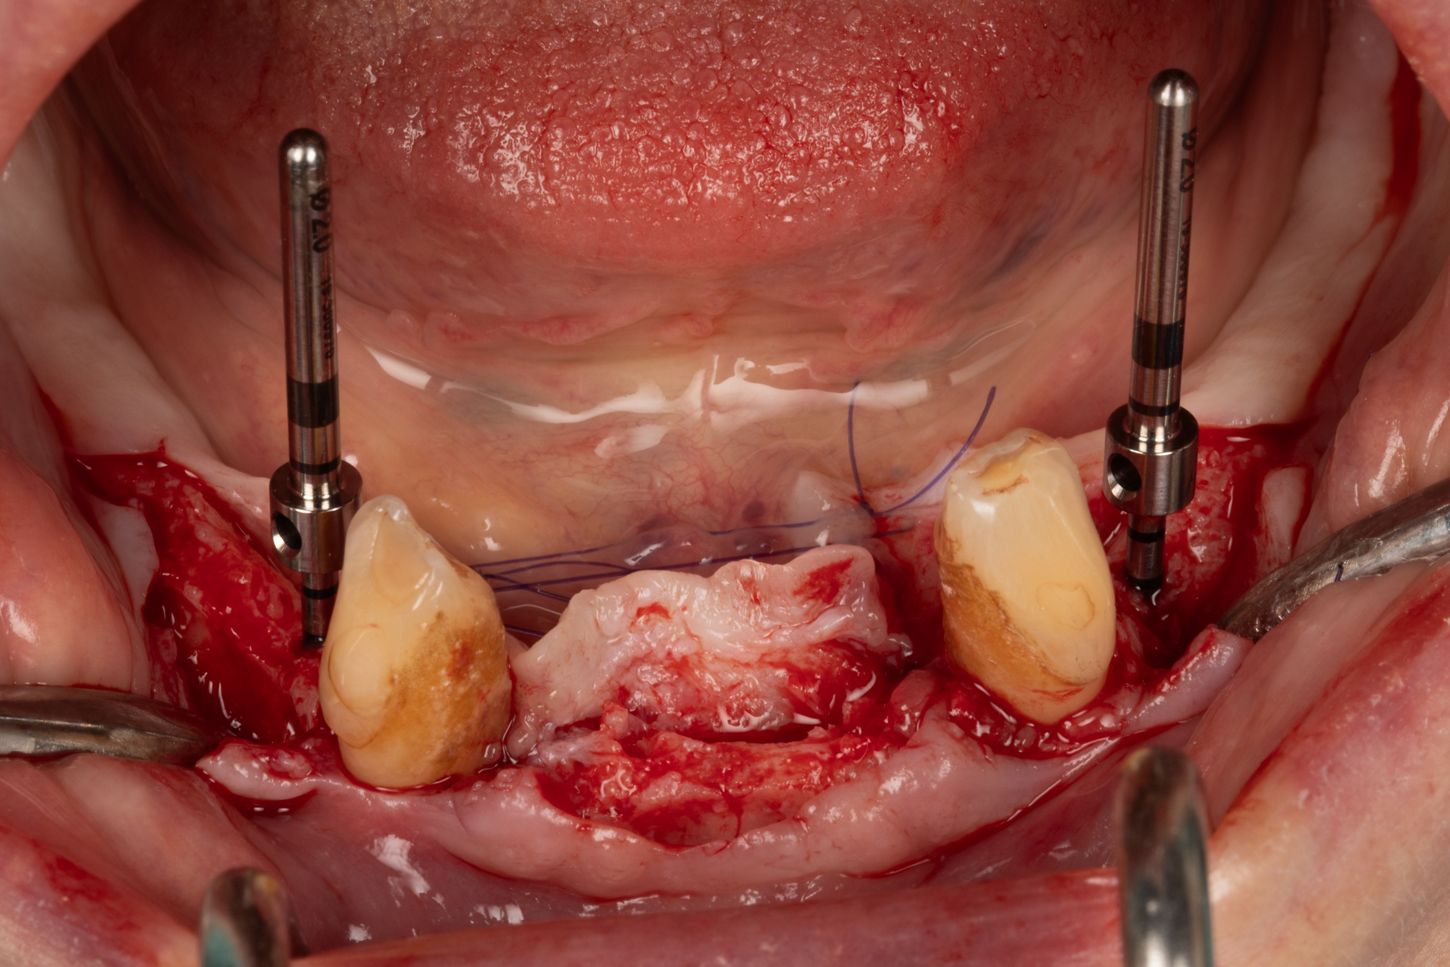

3a. Elevation of the full-thickness flap by crestal incision centred on the keratinised and sulcular tissues in 33 and 43.

The canines are preserved to provide an indication of the drilling axis.

Initial drilling in 32 and 42 using the first 1.5 mm drill bit, then positioning of directional indicators to assist with subsequent drilling. Drilling to 12 mm is checked using the graduation on the initial drill bit.

3b. Drilling adjacent to the remaining teeth 33 and 43 using the initial 1.5 mm drill. Depth and axis checked using the anterior indicators and residual canines.

Given the average bone density (D2 to D3), only the initial drill was used to the working length of 12 mm.